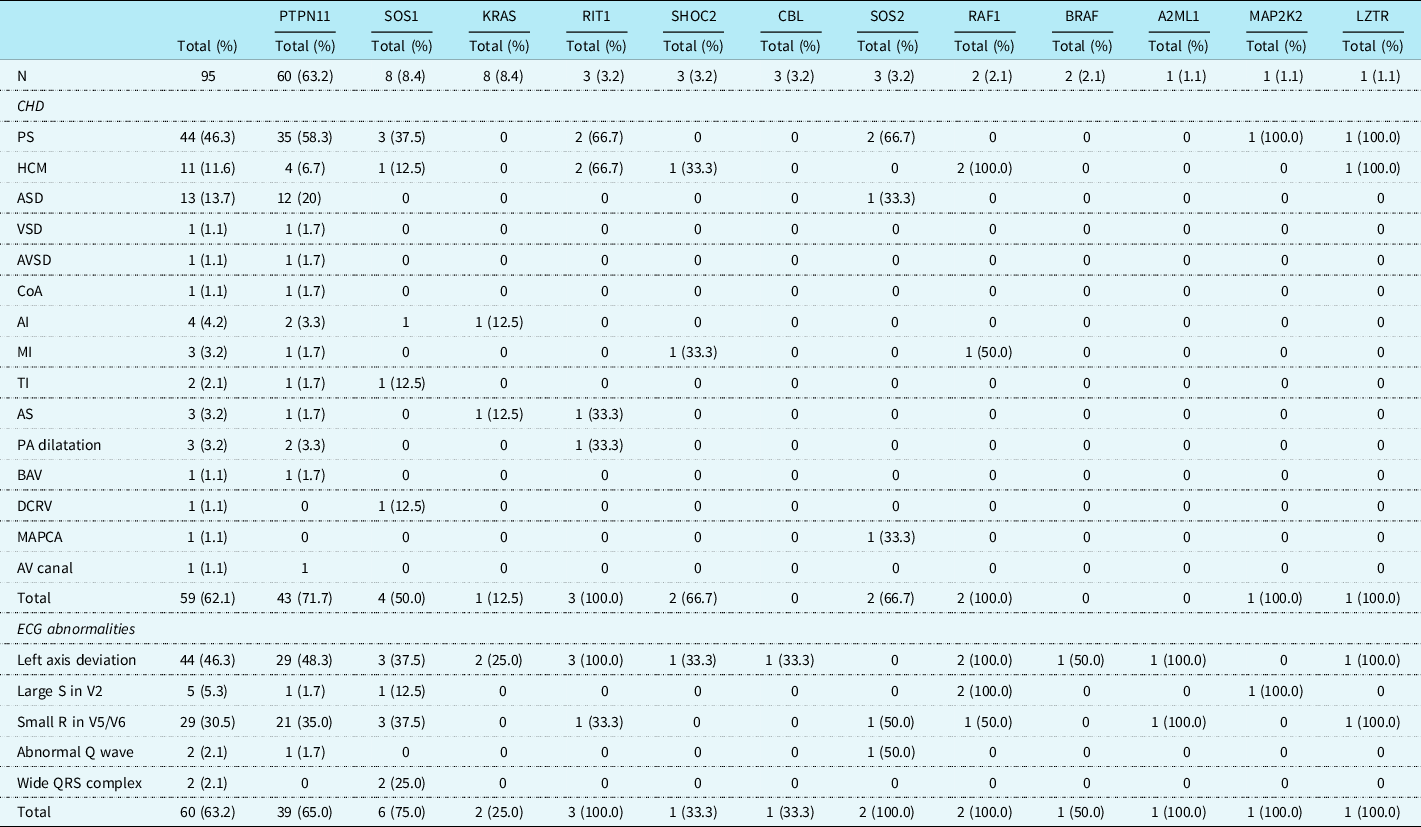

A cohort of 95 patients was included in this study. Of these patients, 46 (48.4%) were male and 49 (51.6%) were female, and their median (IQR) age at the date of the ECG was 4.9 years (0.9–14.4). Table 1 shows the distribution of the involved genes, the cardiac defects, and typical Noonan syndrome-related electrocardiographic features. Sixty (63.2%) of the patients had a mutation in PTPN11, and mutations in SOS1 and KRAS were found in 8 (8.4%) patients.

Table 1. Cardiac heart defects and ECG abnormalities in patients with Noonan syndrome

AI = aortic insufficiency; AS = aortic stenosis; ASD = atrial septal defect; AV = atrioventricular; AVSD = atrial ventricular septal defect; BAV = bicuspid aortic valve; CHD = congenital heart defect; CoA = coarctatio aortae; DCRV = double-chambered right ventricle; ECG = electrocardiogram; HCM = hypertrophic cardiomyopathy; MAPCA = major aortopulmonary collateral artery; MI = mitral insufficiency; PA = pulmonary artery; PS = pulmonary stenosis; TI = tricuspid insufficiency; VSD = ventricular septal defect.

Congenital heart defects

It was possible to use the initial echocardiographic recordings in 55 of the 95 patients. In 40 patients, the recorded diagnosis was used. Fifty-nine (62.1%) patients had CHD. Pulmonary valve stenosis (mild in 53%, moderate 11%, and severe in 36% of the cases; all severe cases had a therapeutic intervention afterwards) was most frequently seen followed by an atrial septal defect (haemodynamically important in 35%, not important 65%) and hypertrophic cardiomyopathy (of which two needed a surgical intervention afterwards), in, respectively, 44 (46.3%), 13 (13.7%), and 11 (11.6%) patients. Pulmonary valve stenosis was most often seen in patients with a mutation in PTPN11 (58.3%), SOS1 (37.5%), RIT1 (66.7%), and SOS2 (66.7%). Patients with a PTPN11 gene mutation had a significantly higher incidence of pulmonary valve stenosis (58.3%) and atrial septal defect (20%) than patients with other gene mutations (respectively, p = 0.003 and p = 0.027). Hypertrophic cardiomyopathy was more frequently diagnosed in patients with mutations of RIT1 (66.7%) and RAF1 (66.7%) genes, which was significantly more frequently than in the other NS genes (respectively, p = 0.035 and p = 0.012).

Electrographic abnormalities

In 60 patients (63.2%), one or more typical Noonan syndrome-related electrocardiographic features were seen. Most of the patients with CHD did show these typical Noonan syndrome-related electrocardiographic features (45/59, 76.3%). Also, in 15 of the 36 (41.7%) patients with a structurally normal heart on echocardiogram, typical Noonan syndrome electrocardiographic abnormalities were detected (Table 1). There was no significant difference in the incidence of the individual-specific Noonan syndrome-related electrocardiographic features between the group with CHD and the group without CHD, however, specific electrocardiographic features as a group occurred significantly more frequently in patients with CHD (p = 0.001).

There were 44 (46.3%) patients with left axis deviation, 29 (30.5%) patients with small R-waves in the left precordial leads, and 5 (5.3%) patients with large right precordial S-waves. An abnormal Q-wave was seen in 2 (2.1%) patients and a wide QRS complex also in 2 (2.1%) patients (Table 2). Typical Noonan syndrome-related electrographic features were not more often seen in patients with a mutation in the PTPN11 gene than in patients with other gene mutations. Patients with a mutation in the RAF1 gene had more frequently large S-waves in the right precordial leads (p = 0.002), and patients with SOS1 gene mutation had more frequent wide QRS complexes (p = 0.006).